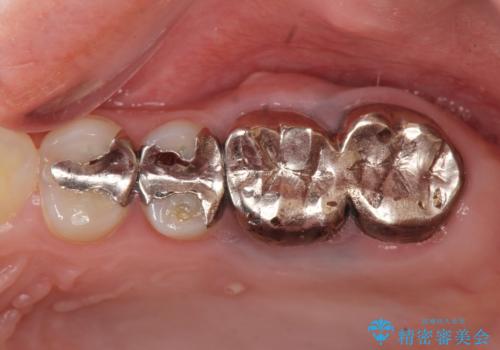

- 「銀歯で被せた歯の歯ぐきが腫れる、痛みが続く。」と痛みの改善を求めて来院されました。

X線検査の結果、左上6には歯根破折、左上7には銀歯の下に大きな虫歯の再発が認められ共に抜歯をせずには症状の改善が見込めない状況です。